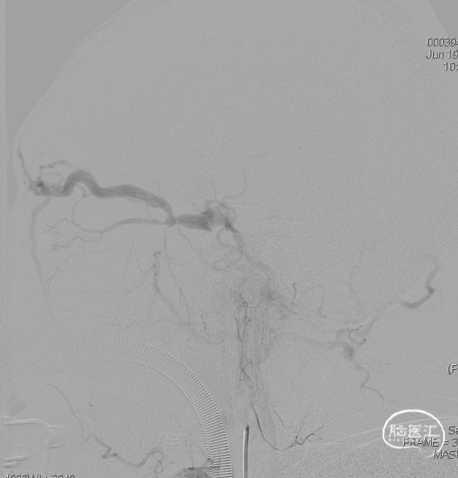

左侧咽升供血的HCDAVF,逆流至海绵窦,经眼上静脉-面静脉引流。

术后造影见瘘口不显影。

术后右侧颈总造影,未见向瘘口供血。